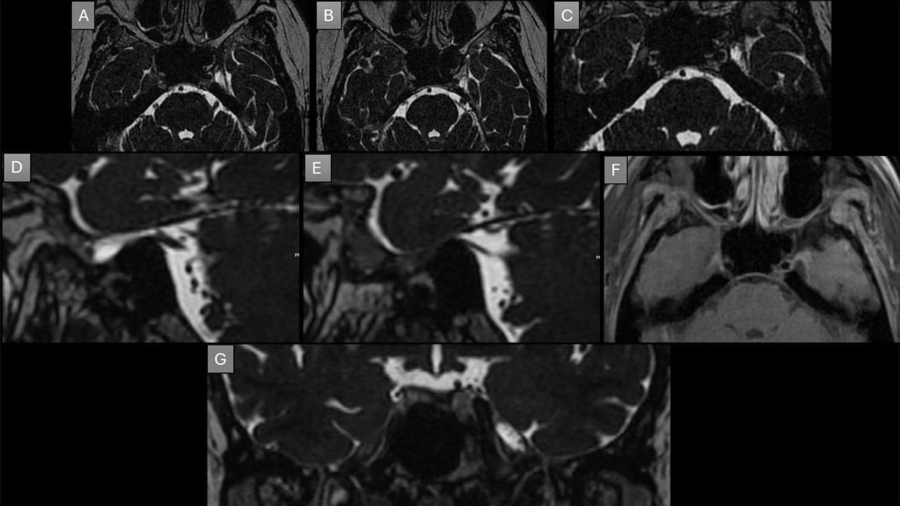

A 29-year-old man complains of neck pain extending to left side of shoulder and diffuse back pain for 5 years.

July 2025